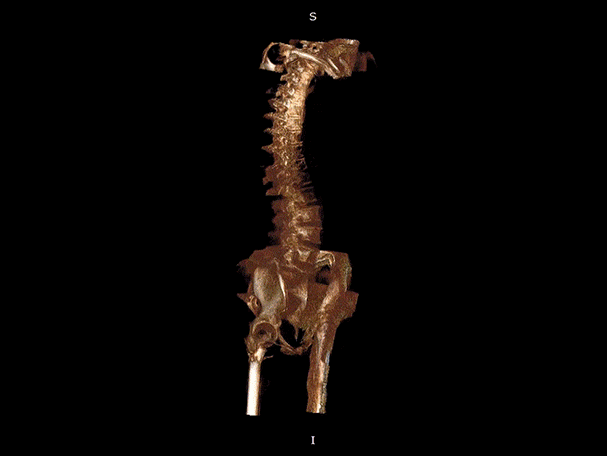

填补常规CT/MR空白

助力术前规划和术后评估

颈椎

腰椎

VR体绘制重建